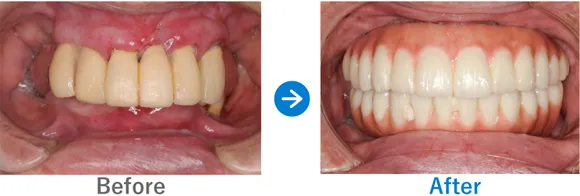

Case2

上下義歯の状態からインプラント治療後に自信を取り戻された方

上下義歯(入れ歯)ほとんど歯が残っていない、残存歯は上顎1本下顎5本のみ。

上顎骨がやせていて普通にはインプラントが出来ない状態。

上顎ザイゴマインプラントでALLON4、下顎ALLON4

10,703,000円(上顎7,128,000円、下顎3,575,000円/内訳:上顎オールオン4(ノーベルザイゴマインプラント4本)、下顎オールオン4(ストローマンインプラント4本)、3Dモデルガイド*、仮歯、セデーション、ボツリヌストキシン注射、3D模型、保証10年)

来院の背景

60代前半から現在の義歯を使っている。初めはピッタリだったが、だんだんと義歯がゆるくなり、鈎歯(こうし)が折れた。歯がダメになったら、インプラントを検討しようと思っていた。ご主人のご友人がインプラントをしたため興味を持ったが、金額もかかるため、家族には相談せずに来院された。

治療結果

上顎ザイゴマインプラント4本。下顎ALLON4で行った。治療完了後、現在もメンテナンスで来院中で経過良好。口元が綺麗になり、お化粧をするなど美意識が高まり、おしゃれに気をつかうようになったとのこと。「笑顔が増えて、よく外出するようになりました。自信がつきました。」